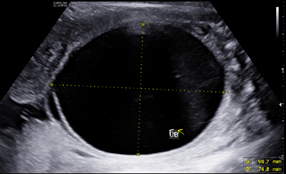

A 25-year-old G2P1001 at 19w2d presented for anatomic ultrasound. Routine prenatal genetic screening indicated an elevated risk for Down syndrome, 1:259. Her prenatal course was otherwise uncomplicated. Initial anatomical evaluation noted adequate amniotic fluid, a markedly distended fetal urinary bladder, moderate-to-marked bilateral renal hydronephrosis, a moderate degree of bilateral hydroureter, and bilateral renal cortical cysts, (Figures 1-4). Patient was sent for second opinion with secondary survey, within 1 week, denoting bladder outlet syndrome with oligohydramnios. A characteristic "keyhole" sign was noted (Figure 5). Patient initially elected for genetic non-invasive prenatal testing and later for genetic amniocentesis, the results of which revealed a normal karyotype/FISH/microarray. At the time of amniocentesis, bladder tap was performed and yielded 160cc of fluid for evaluation of renal function based on urine sodium, chloride, urine osmolality and calcium levels. At 22w3d patient presented for follow up sonographic evaluation; findings revealed significant fetal abdominal ascites, persistent oligohydramnios, a "bell-shaped" chest with only the left lung measurable, and the right lung poorly defined. Bilateral urinary tract dilation was again observed, with the right kidney measuring 2.0 x 3.0cm and the left kidney measuring 2.3 x 1.7cm. The kidneys were echogenic in nature and the parenchyma was thickened up to 7mm, with no pyramids visible. The bladder had severe thickening, measuring up to 7.7mm in diameter. The bladder measured 4.7 x 1.7cm with intraluminal calcifications noted both in the bladder and intestines. The patient was counseled on these new findings and concern for both pulmonary hypoplasia and possible poor renal function. The patient was given the option to proceed with fetal urinary evaluation for renal function and possible bladder shunt vs termination of pregnancy secondary to these findings; she elected for pregnancy termination.1–3

Figure 2 Moderate-to-marked bilateral renal hydronephrosis.

The presence of a posterior urethral valve prevents normal fetal micturition, resulting in bladder distension and subsequent distension of the ureters and kidneys. Diagnostic features of posterior urethral valves on sonography varies, but classically presents in male fetuses with fetal megacystis that may fill the entire abdomen, thickened bladder wall (>3mm) with prominent trabeculae, oligohydramnios, and bilateral hydronephrosis with hypoechoic renal parenchyma and/or cortical cysts that can indicate renal dysplasia. The best diagnostic clue is the presence of a dilated posterior urethra (“keyhole” sign) . While not always seen, its presence, suggests the diagnosis of PUV. These findings however, may be found in other urinary tract conditions. Megacystis is defined as a longitudinal bladder diameter (LBD) > 7mm in the first trimester. However, after the first trimester, it is most commonly defined as failure of bladder emptying during a 45min period of ultrasound examination.5